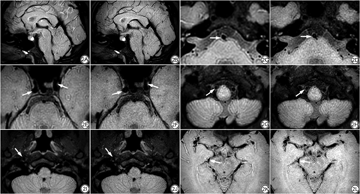

在轴位上进行感兴趣区(region of interest, ROI)勾画测量(图1),为保证ROI大小形状一致,采用复制-粘贴ROI的方式进行勾画。SI测量:SI脑白质将ROI放置在半卵圆中心,SI脑灰质将ROI放置在背侧丘脑,SI脑脊液将ROI放置在第四脑室,SI颞肌将ROI放置在颞肌最大层面,四者的ROI面积均为20 mm2;SD背景测量:以脑白质为背景,将面积为100 mm2的ROI放置在半卵圆中心。以上除第四脑室测量两次取平均值外,其余组织均左右两侧对称测量并取平均值。由于使用并行采集技术得到的图像的噪声分布是非均匀的,故没有直接测量背景中空气的噪声,而以脑白质的信号的标准差作为背景噪声[13]。计算CNR时以颞肌信号作为对照,计算公式为:SNR组织=SI组织/SD背景,CNR组织-颞肌=(SI组织-SI颞肌)/SD背景(SI组织为各组织的信号平均值,组织包括脑白质、脑灰质和脑脊液)。

所有评分指标优化后得分较优化前得分增高。整体图像质量、右侧椎动脉V4段、基底动脉、右侧颈内动脉C1段、双侧颈内动脉C4段、双侧大脑后动脉P2段的管腔管壁优化后图像质量优于优化前图像质量,优化前、后图像质量差异具有统计学意义(P<0.05);左侧椎动脉V4段、左侧颈内动脉C1段、双侧大脑前动脉A1段及A2段、双侧大脑中动脉M1段及M2段、双侧大脑后动脉P1段的管腔管壁图像质量优化前、后差异无统计学意义(P>0.05)(表1、图2)。两名诊断医师主观评分的Kappa值为0.989(P<0.05),一致性优异。

整体图像质量主观评分在参数优化后得分明显增高,脑干、脑实质的噪声稍有减小,对小脑纹理显示也更加清晰。在管腔管壁显示方面,纳入研究的所有血管节段优化后得分均比优化前有所增高。右侧椎动脉V4段、基底动脉、右侧颈内动脉C1段、双侧颈内动脉C4段、双侧大脑后动脉P2段的管腔管壁优化后图像质量明显优于优化前,对血流信号抑制效果更好。虽然左侧椎动脉V4段、左侧颈内动脉C1段、双侧大脑前动脉A1段及A2段、双侧大脑中动脉M1段及M2段、双侧大脑后动脉P1段的管腔管壁图像质量优化前、后差异不大,但均能对管腔管壁有较好的显示,满足临床诊断要求,且扫描时间大幅缩短,故本研究在以上血管节段仍然是有意义的。优化后序列对大脑前、中、后动脉血管显示均较好,但仍对部分血管节段显示欠佳,对椎动脉显示欠佳的原因为椎动脉靠近头颅线圈边缘,由于近线圈效应,信号较弱;而对基底动脉和颈内动脉显示欠佳是由于头颅岩部空气和颅骨的干扰,不同物质交界处磁化率相差较大,局部磁场不均匀,产生磁敏感伪影[32]。